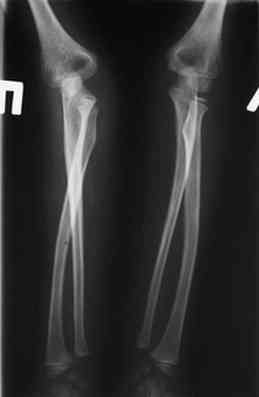

2 По снятии аппарата через 2 мес после операции рефрактура в месте остеотомии(на фоне активного ротационного движения)- под контролем ЭОП выполнен

интрамедуллярный остеосинтез TEN. Положение головки луча стабильное.